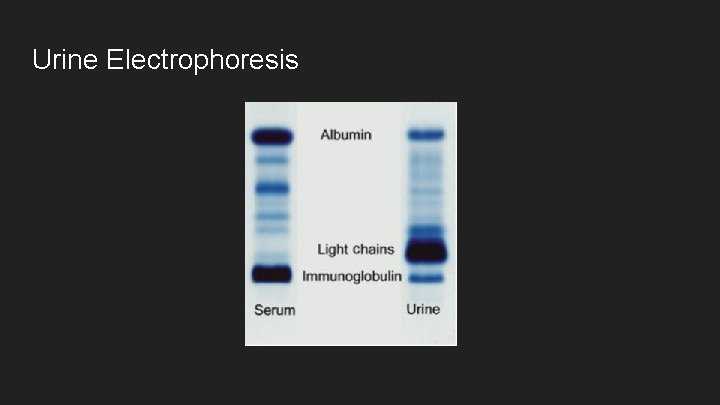

Urine Electrophoresis